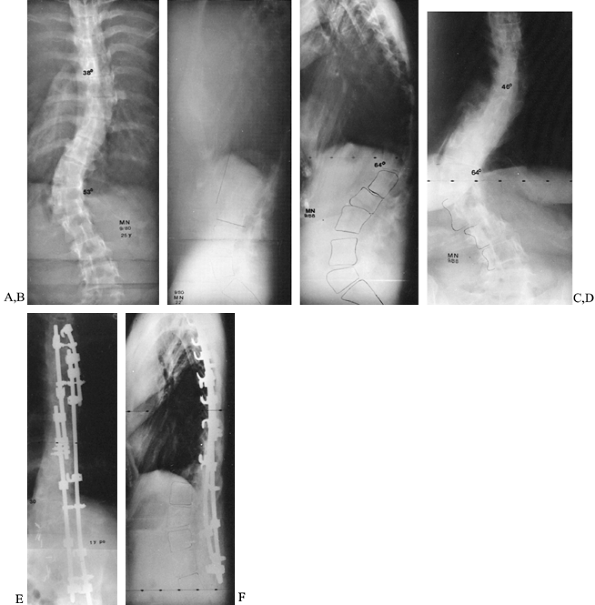

thoracolumbar junction (7). Anterior release and fusion should be added in such cases (Fig. 158.8)

![]() |

Figure 158.8. Progressive kyphoscoliosis in Marfan syndrome. A,B: Posteroanterior and lateral films at age 25, with 53° thoracolumbar scoliosis and 22° kyphosis. C,D: Repeat films 8 years later (after two pregnancies) show increase of scoliosis to 64° and, especially, of kyphosis to 64°. E,F:

One year after anterior release and fusion and posterior fusion with Cotrel-Dubousset instrumentation. Note that standard rods were not long enough in this patient; longer rods may be specially ordered. |

mind include the following: (a) The rate of dural ectasia is high (63%)

double curves in these already tall patients may require special ordering of long rods (Fig. 158.8).